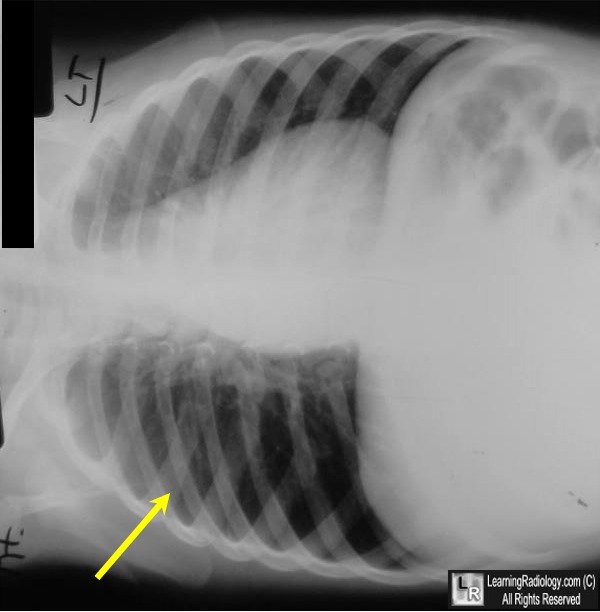

Aspirated Foreign Body (peanut). Upper photo There is unilateral

From www.learningradiology.com